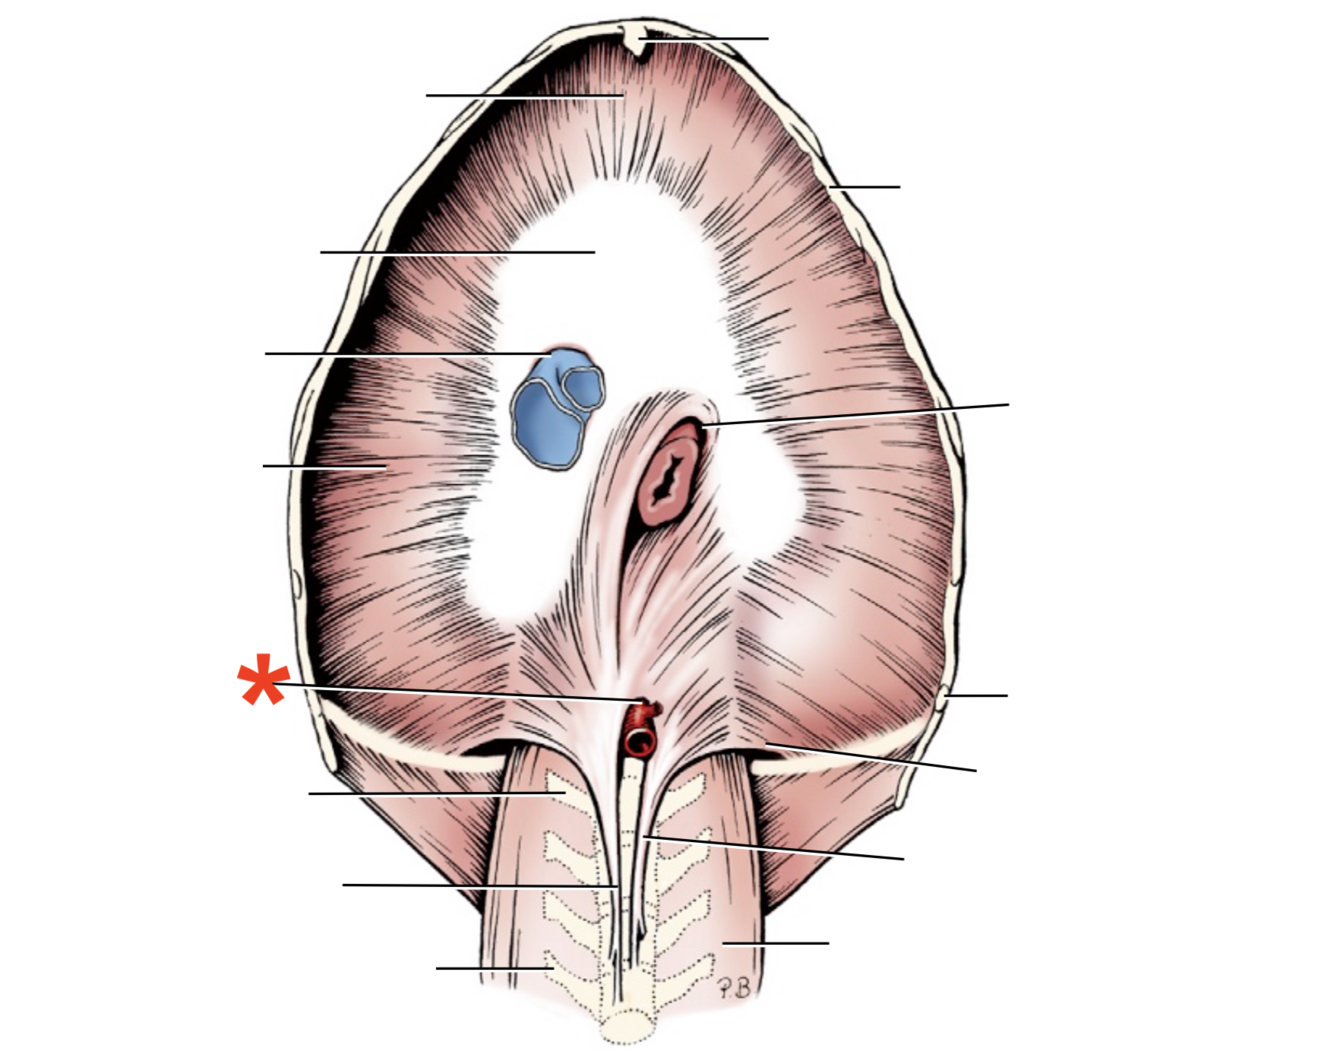

1

Q

Name given to the most cranial part of the diaphragm.

A

Cupula Diaphragmatis

2

Q

A

Pars sternalis

3

Q

A

Foramen vena cavae

4

Q

A

Pars costalis

5

Q

A

Hiatus aorticus

6

Q

A

Arcus lumbocostalis

7

Q

A

Hiatus oesophagus

8

Q

A

Crus sinistrum

9

Q

A

Crus dextrum

10

Q

A

Centrum tendineum

11

Q

A

Corona muscularis